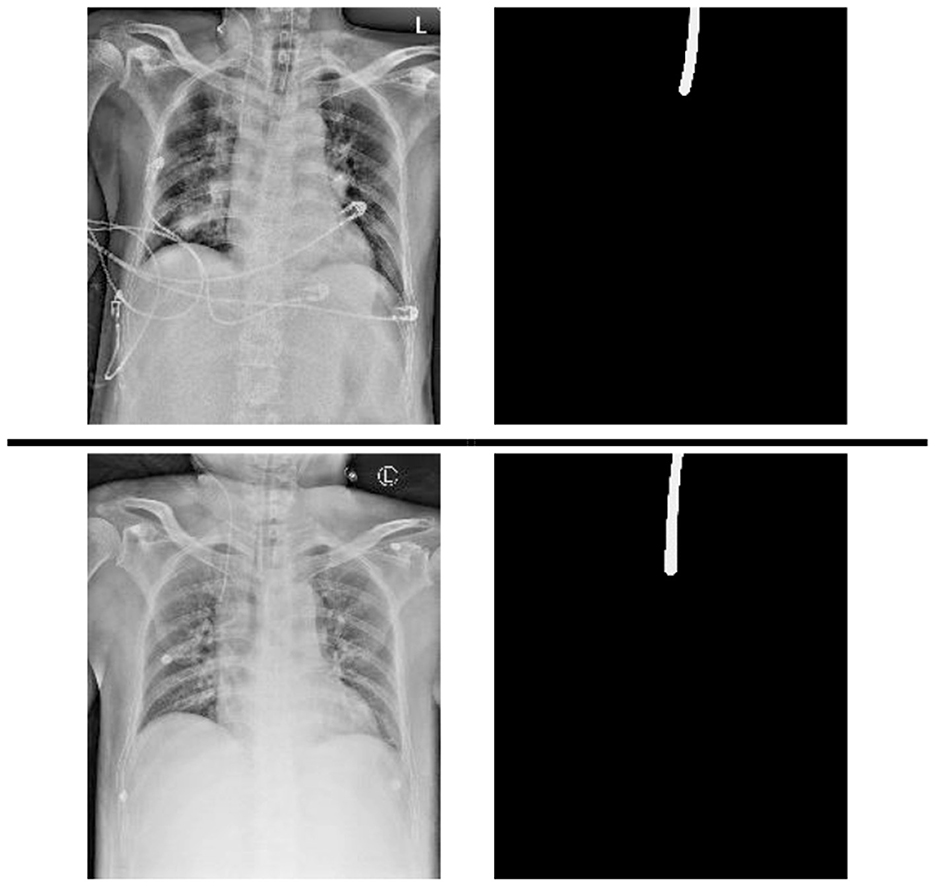

A chest x-ray dataset was applied to analyze the impact of the proposed method. The data were collected from chest radiographs of intubated ICU patients which had been confirmed by doctors from the Dalin Tzu Chi Hospital and who corrected the ground truth (see Figure 2).

The deviation of 5-fold cross validation is shown in Table 1, where 144 additional images from the Royal Australian and New Zealand College of Radiologists (RANZCR) Catheter and Line Position (CLiP) challenge dataset (Jarrel Seah et al., 2023) are also added to the training dataset of each fold. This study was approved by the institutional review board (IRB) of the Buddhist Dalin Tzu Chi Hospital (IRB number: B11103010).